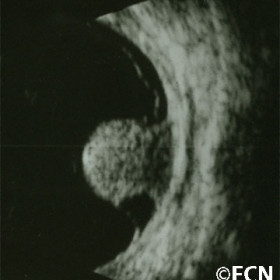

Choroidal Hemangioma

Choroidal Hemangioma - Moderately high internal reflectivity and a "dome" shape are typically revealed by ultrasound imaging of choroidal hemangioma.